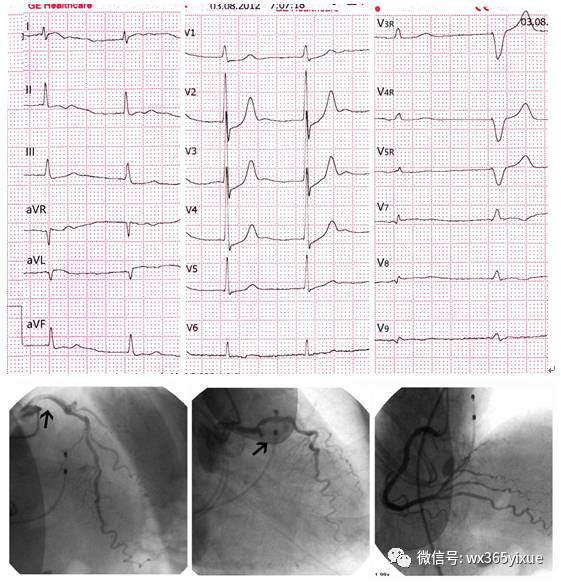

图4患者女,75岁,因“胸痛8小时”入院。

发现血压高3年。查体:血压145/90mmHg;神清,双肺呼吸音粗,双下肺闻及细湿罗音,未闻及干罗音,心率104次/分,心律绝对不齐,第一心音强弱不等,未闻及病理性杂音。入院心电图示:心房颤动,临时起搏。V1-V6呈R型,I、aVL和V7-9导联(第一个自身的QRS波群)显示出ST段抬高0.05-0.1mV。Ⅱ、Ⅲ、aVF导联ST段压低0.05-0.1mv,V1-6导联ST段压低0.1-0.3mV。冠状动脉造影显示回旋支近段完全闭塞(箭头指示)。